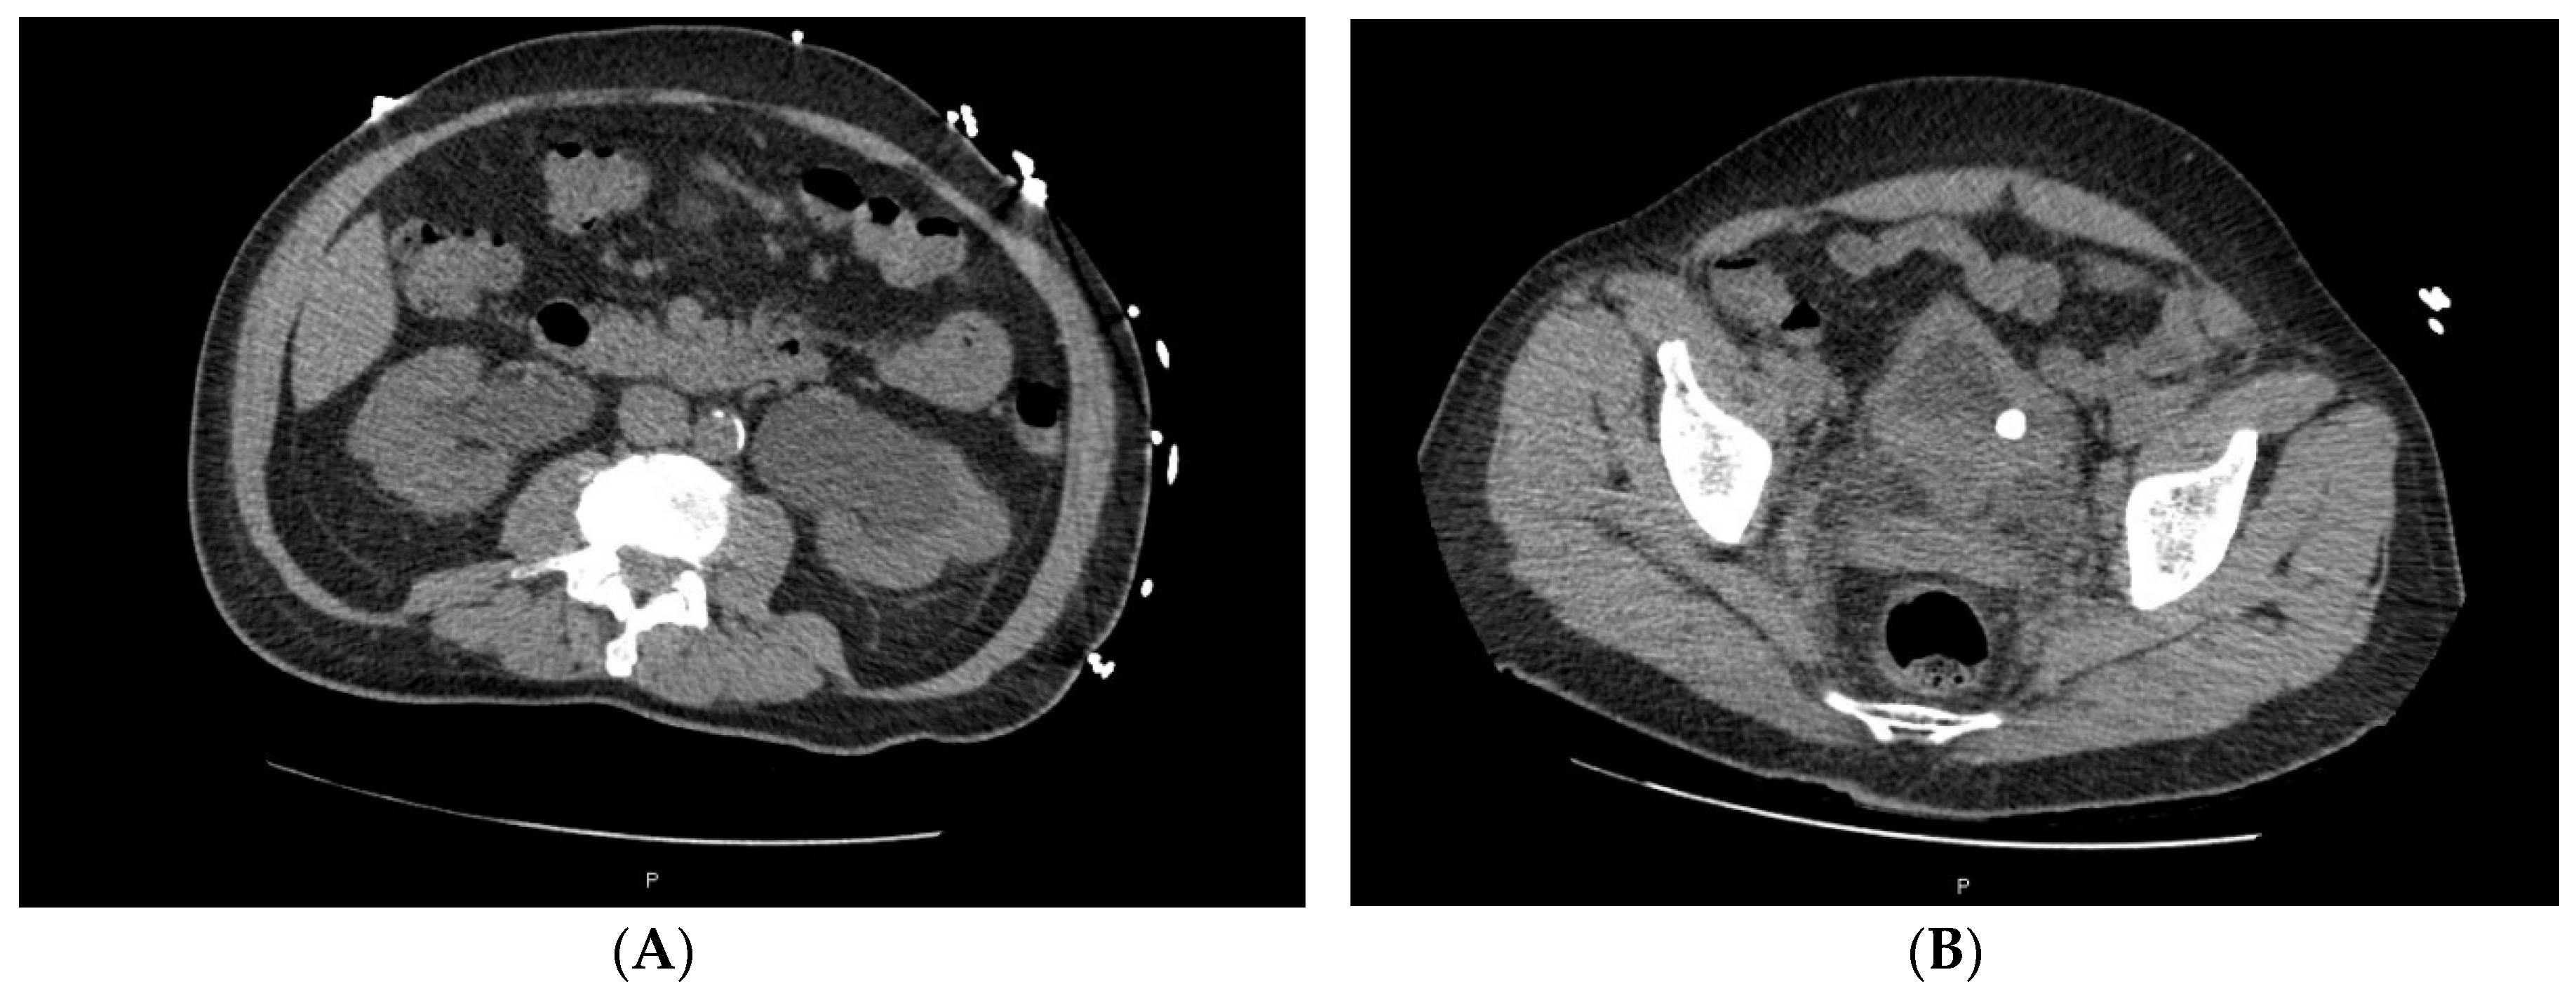

2. Case Series